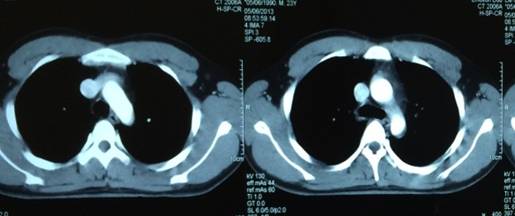

Hình ảnh chụp CT ngực không phát hiện hạch trung thất.

Tầng ngực: Không có hạch trung thất